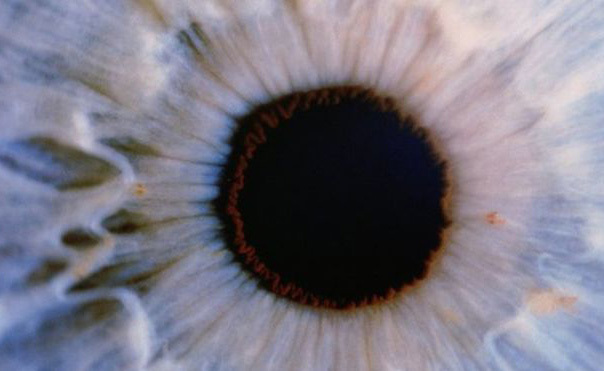

Un’intervento innovativo effettuato a Londra ha ridato la vista a una paziente affetta da cecità (AMD). Ma è davvero stata trovata una cura per questa grave patologia?

Questo intervento avvenieristico è stato messo a punto dal team del London Project to Cure Blindness, usando un tappeto cellulare che è stato iniettato nell’occhio di una donna affetta da degenerazione maculare, o AMD. Le cellule utilizzate sono di tipo staminale, che bene si prestano a questo scopo.

Questa particolare tipologia di cellule, che sono considerate immature e possono quindi crescere in ogni parte del corpo, ha un’origine embrionale. Una volta usate su di un patch sono destinate a formare l’epitelio pigmentato retinico, uno strato di cellule che riveste la parte posteriore dell’occhio, nutre e sostiene altre cellule e che ci permette di vedere i colori e le immagini nel nostro campo visivo centrale. I pazienti affetti da AMD, infatti, sono proprio colpiti in questo aspetto, dove la loro visione centrale diviene distorta. I medici sono propensi a credere che riparare l’epitelio retinico danneggiato possa porre rimedio alla patologia.